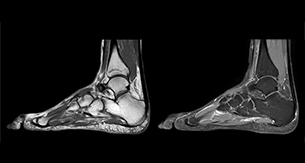

“In peripheral joints, mDIXON TSE imaging aids in diagnosing injuries in ligaments or tendons, for imaging degenerative and inflammatory pathologies such as osteoarthritis and rheumatologic disorders and for oncological exploration.” “For tendon and ligament assessment around knee, ankle, hip and elbow, mDIXON TSE contributes to diagnostic confidence thanks to having images both with and without fat suppression – and without time penalty. This is possible because 2-point mDIXON is faster than the common 3-point Dixon method. It can also increase efficiency as it helps avoid having to add scans during the exam.”

“In peripheral joints, we get good image quality in difficult areas with mDIXON TSE.

Fat suppressed images appear homogeneous over the entire image, even with large coverage at 3.0T – for instance in scapular or hip girdles – or in the bearing areas or around metal prostheses, where fat suppression is often deficient with STIR or spectral fat suppression, causing diagnostic difficulties. If a diagnostic image is right the first time, we don’t need to repeat or add a sequence.” “mDIXON TSE sequences allow simultaneous characterization of morphological changes from the in-phase T2-weighted images and visualization of edematous changes, thanks to the water T2-weighted images from the same acquisition. Anatomical and morphological considerations could be a partial or complete ligament tear, a bony avulsion or hematoma.” “For soft tissue assessment mDIXON brings similar benefits. For example in one T2-weighted mDIXON TSE acquisition, having the multiple contrasts helps us assess abnormalities in peripheral nerves fascicles, which may be due to anatomical or inflammatory changes..”